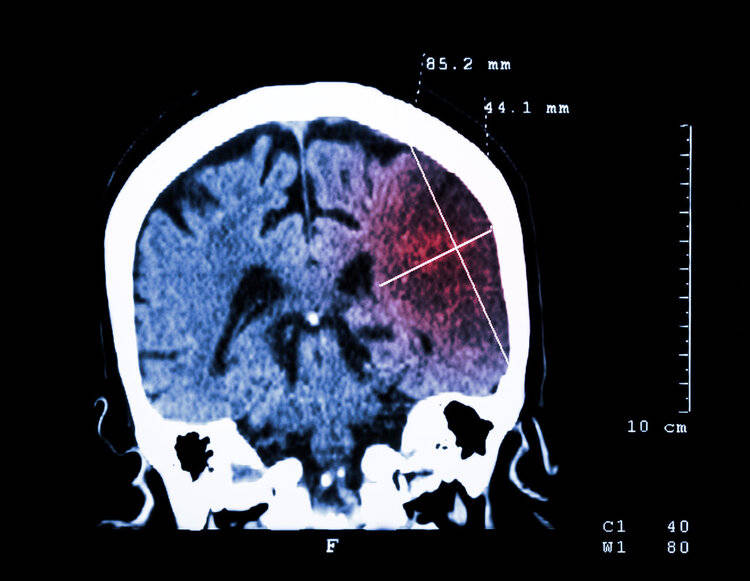

经检查大爷血压高达180mmHg,结合大爷有高血压病史,又出现口角歪斜、肢体无力等表现,最后诊断为脑出血,需要立刻手术降压。医生提醒这已经不是第一个因为高血压引发脑出血的病例了。

其实高血压长期对血管的冲击会让血管失去弹性,增加血管僵硬度,使得血管变得更加脆弱。尤其是脑血管在不稳定的血压影响下更容易出现破裂、阻塞等风险,随着脑血管壁持续增厚,管腔变窄,短期内血压的飙升会使得脑血管出现急性破裂或闭塞,脑卒中、脑出血也会随之而来。